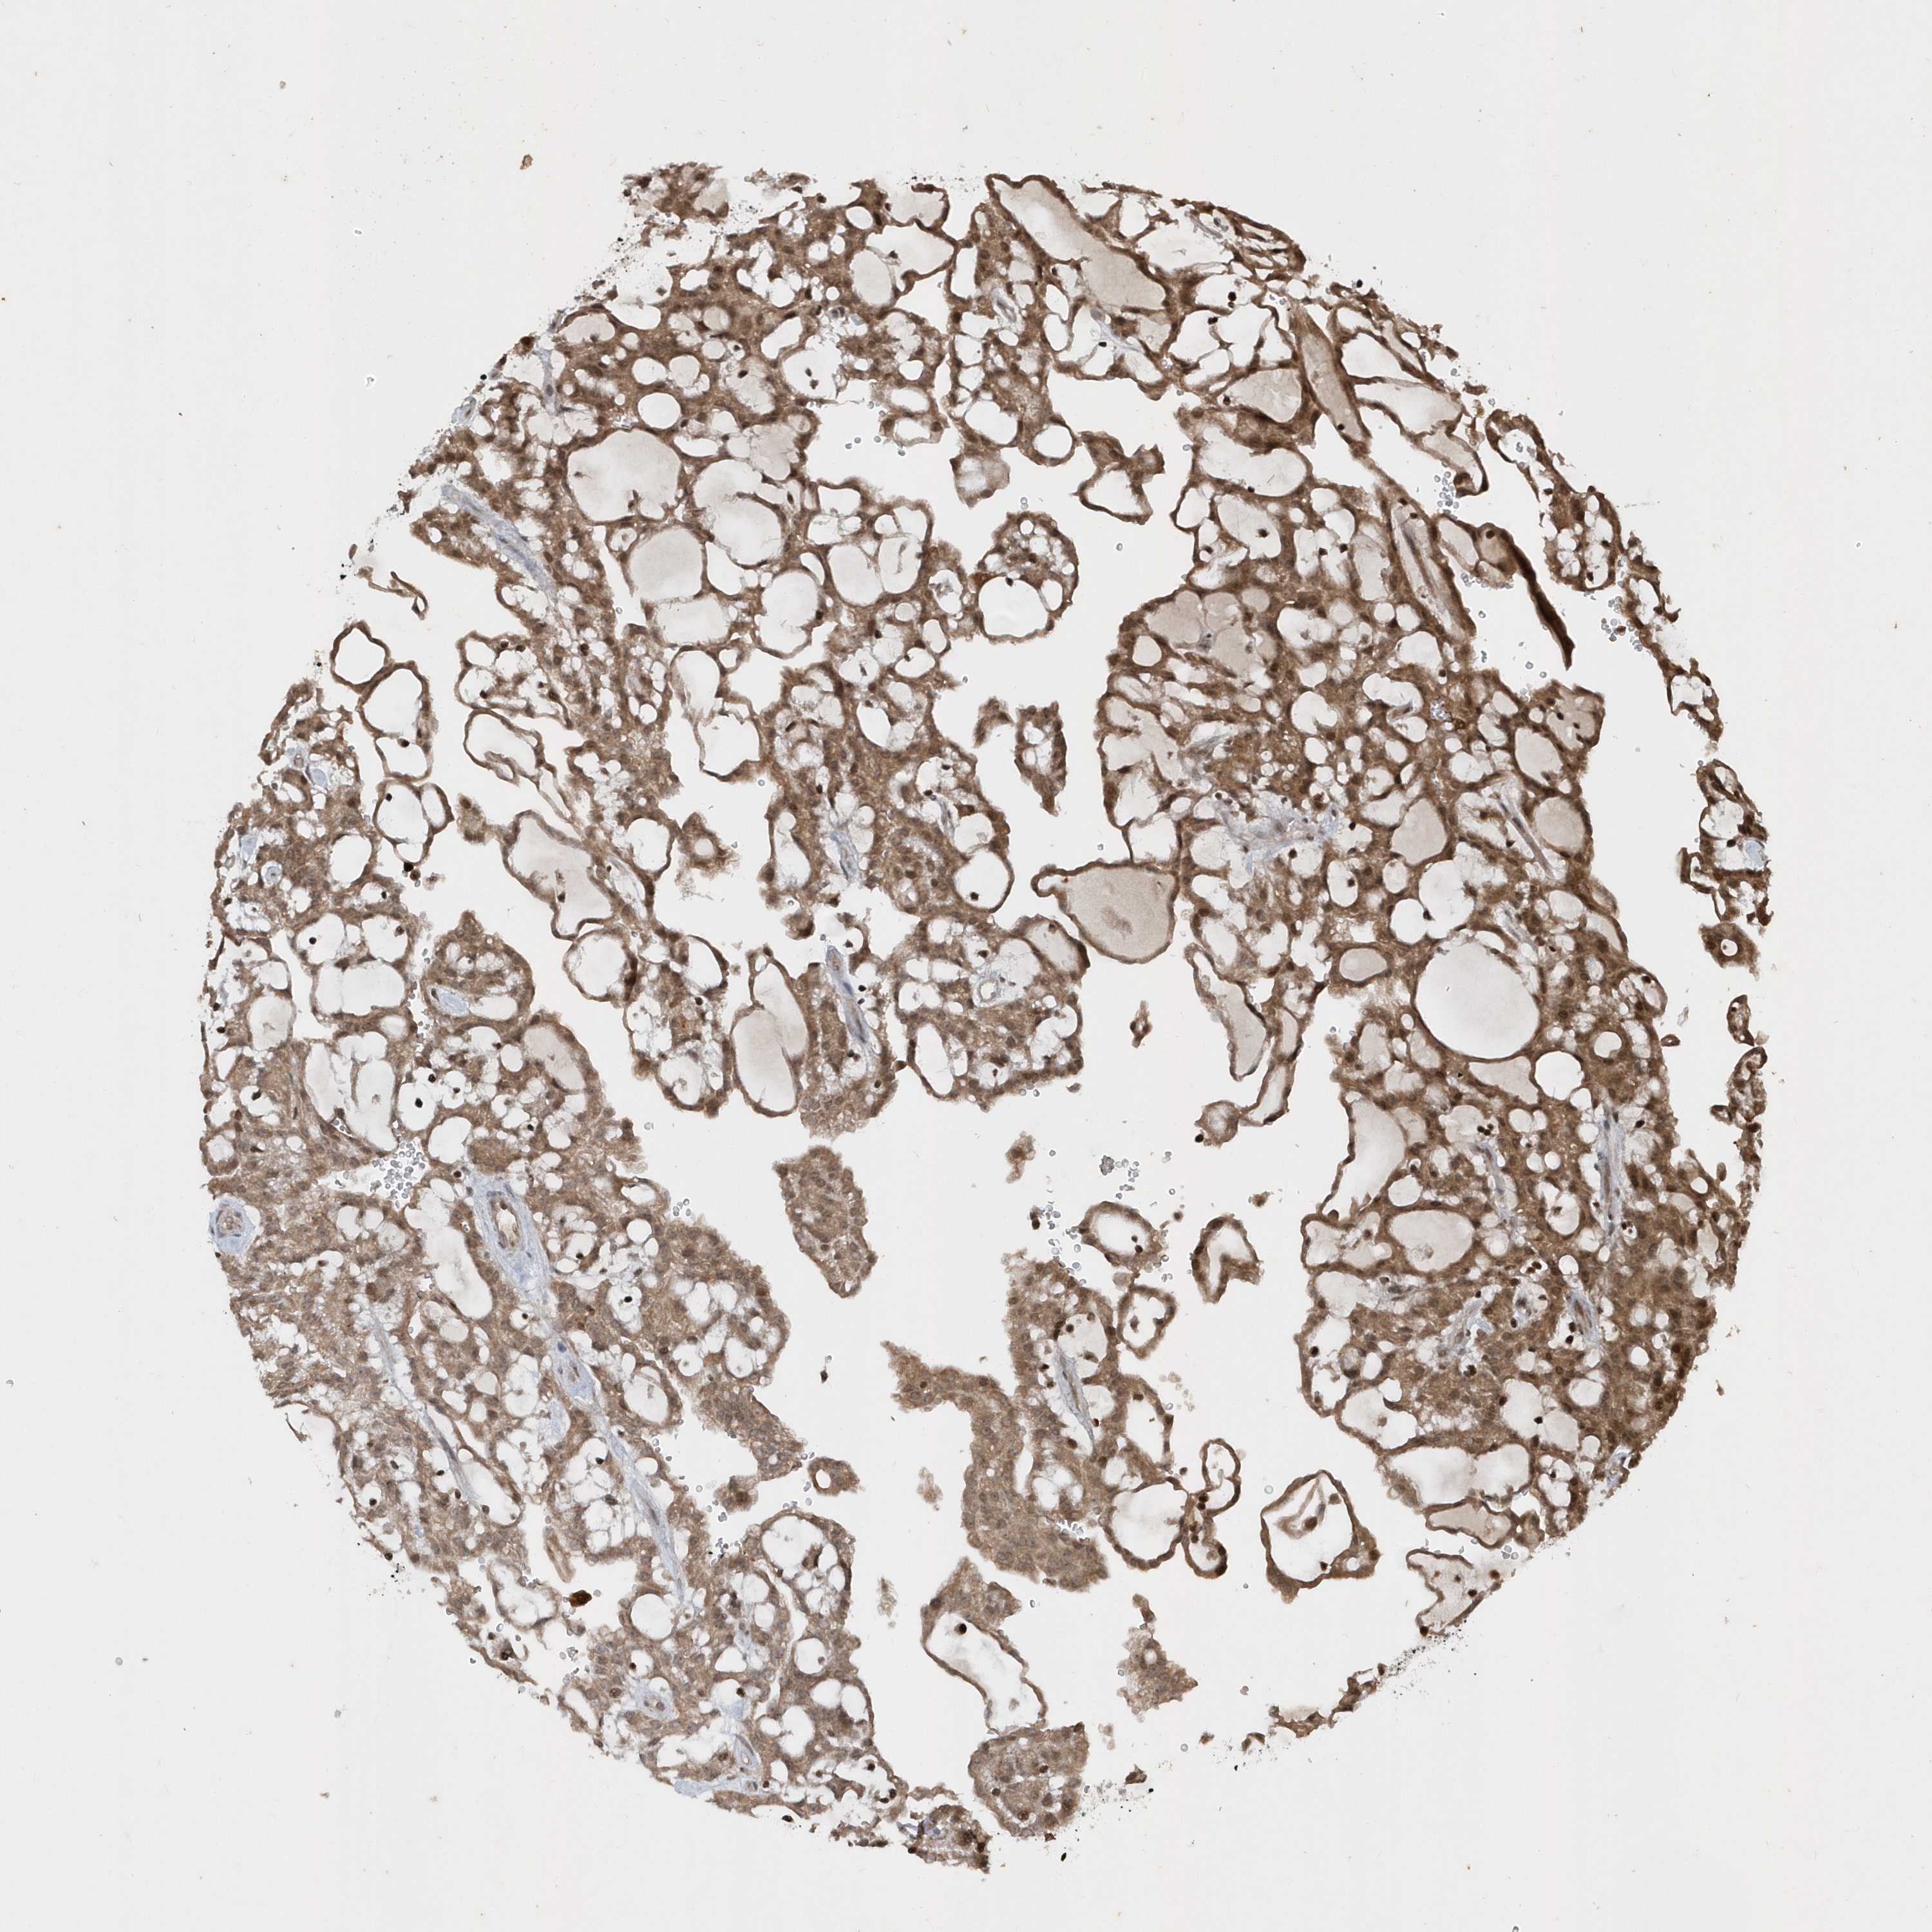

KIDNEY RENAL PAPILLARY CELL CARCINOMA (TCGA) - Interactive survival scatter ploti

The Survival Scatter plot shows the clinical status (i.e. dead or alive) for all individuals in the patient cohort, based on the same data that underlies the corresponding Kaplan-Meier plots. Patients that are alive at last time for follow-up are shown in blue and patients who have died during the study are shown in red.

The x-axis shows the expression levels (FPKM) of the investigated gene in the tumor tissue at the time of diagnosis. The y-axis shows the follow-up time after diagnosis (years). Both axes are complimented with kernel density curves demonstrating the data density over the axes. The top density plot shows the expression levels (FPKM) distribution among dead (red) and alive patients (blue). The right density plot shows the data density of the survived years of dead patients with high and low expression levels respectively, stratified using the cutoff indicated by the vertical dashed line through the Survival Scatter plot. This cutoff is automatically defined based on the FPKM cutoff that minimizes the p-score. The cutoff can be changed by dragging the vertical line or by entering a cutoff value in the square labeled "Current cut-off".

Under the Survival Scatter plot the p-score landscape (black curve; left axis) is shown together with dead median separation (red curve; right axis). Dead median separation is the difference in median mRNA expression between patients who have died with high and low expression, respectively. It is calculated as follows: median FPKM expression of dead patients with high expression - median FPKM expression of dead patients with low expression. This is intended to aid the user in visually exploring custom cutoffs and the associated p-scores and dead median separation.

Individual patient data is displayed and can be filtered by clicking on one or more of the category buttons on the top of the page. Categories describing expression level and patient information include: high, low, alive, dead, female, male and tumor stages. The scale of the x-axis can be toggled between linear and log-scale by clicking on the "x log" button. Mouse-over function shows TCGA ID, patient information and mRNA expression (FPKM) for each patient.

& Survival analysisi

Kaplan-Meier plots summarize results from analysis of correlation between mRNA expression level and patient survival. Patients were divided based on level of expression into one of the two groups "low" (under cut off) or "high" (over cut off). X-axis shows time for survival (years) and y-axis shows the probability of survival, where 1.0 corresponds to 100 percent.

EIF2B1 is not prognostic in Kidney Renal Papillary Cell Carcinoma (TCGA)